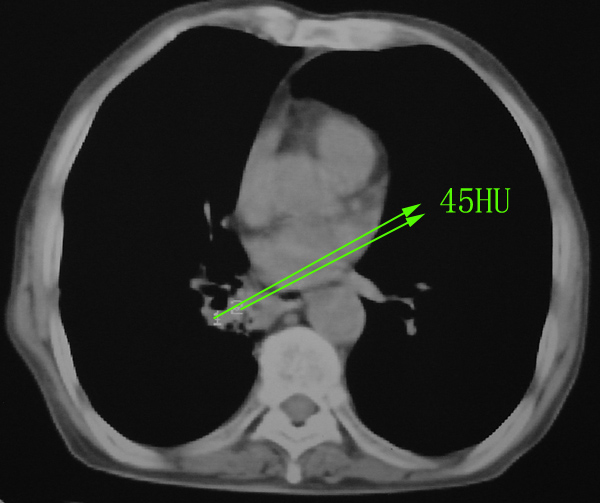

右肺下叶沿着支气管根部见不规则软组织密度影,支气管壁不规则增厚,增强轻度强化.患者年龄偏大,结合临床:多考虑:支气管内膜癌.

右肺下叶沿着支气管根部见不规则软组织密度影,支气管壁不规则增厚,增强轻度强化.患者年龄偏大,结合临床:多考虑:支气管内膜癌.病人已经抗炎治疗4个月了,再抗炎治疗也是这样。